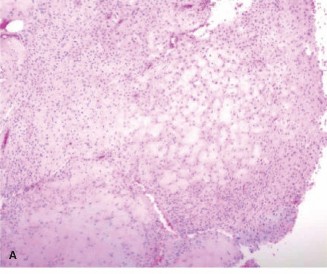

Histological analysis of the core biopsy specimens revealed a distinctly lobulated architecture. The lobules were composed of a biphasic population of cells set within a variably myxoid and chondroid background matrix. At the periphery of these lobules, there was increased cellularity consisting of spindle-shaped and stellate cells. The intervening stroma between the lobules was highly vascularized and fibrous, occasionally containing multinucleated giant cells.

Importantly, while mild cellular atypia and pleomorphism were noted—a common finding in chondromyxoid fibroma that can lead to misdiagnosis—there were no atypical mitotic figures, and no frank anaplasia or permeative growth patterns characteristic of malignancy were observed. The synthesis of the clinical, radiographic, and histopathological data definitively confirmed the diagnosis of a Chondromyxoid Fibroma.